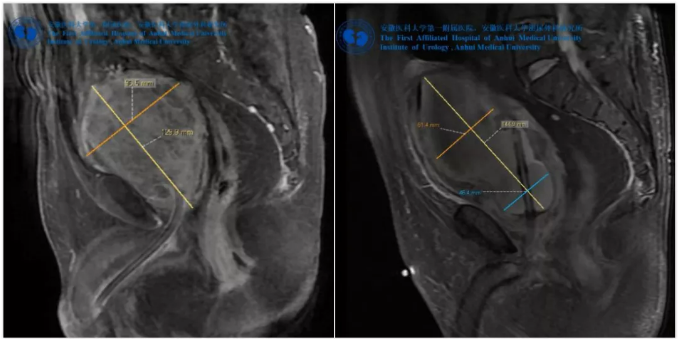

(左)術(shù)前盆腔MRI示前列腺573.7克,(右)術(shù)后第二天MRI示增生前列腺腺瘤完整去除

由于前列腺體積過大,無醫(yī)院愿意為其手術(shù)治療,后經(jīng)上海某醫(yī)院做了經(jīng)尿道前列腺電切術(shù),半年再后次排尿困難并出現(xiàn)下腹脹痛, MRI檢查發(fā)現(xiàn)前列腺體積已經(jīng)增大至573.7克,術(shù)后不到一年,前列腺體積又增加了200克以上。

手術(shù)順利完成,患者術(shù)后膀胱沖洗一直如清水,充分體現(xiàn)醫(yī)生的高超技藝和司邁等離子獨特、可靠的止血效果,術(shù)后第二天患者即恢復(fù)正常飲食,并開始下床活動,配合完善術(shù)后盆腔MRI檢測。